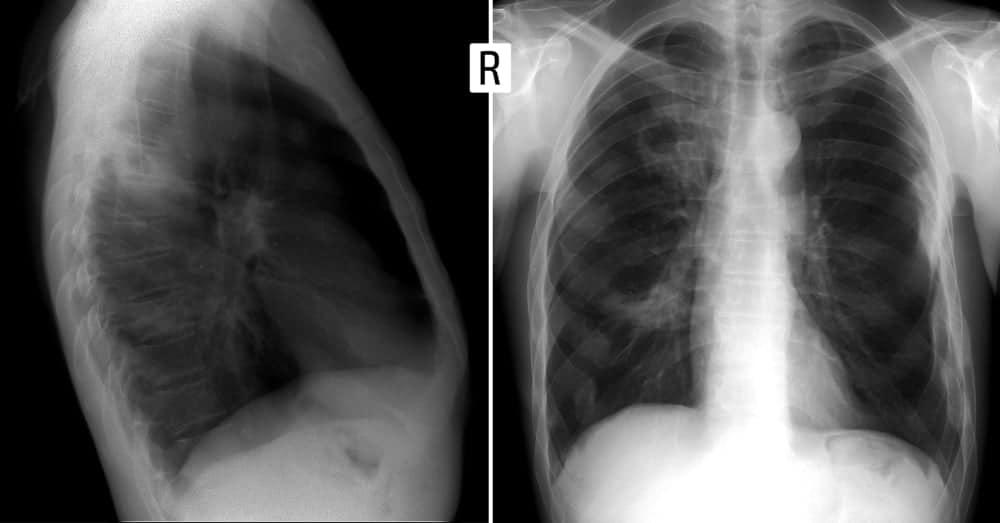

Chẩn đoán

Đầu tiên, bác sĩ sẽ khám các triệu chứng và hỏi về tiền sử bệnh nhân. Sau khi đánh giá lâm sàng, bác sĩ có thể chỉ định một số kỹ thuật cận lâm sàng như:

- Chụp X-quang ngực thẳng hoặc cắt lớp vi tính ngực (CT scan)

- Dẫn lưu tư thế vỗ rung lồng ngực: Dựa vào phim chụp X-quang phổi thẳng nghiêng để chọn tư thế dẫn lưu, vỗ rung lồng ngực cho người bệnh.